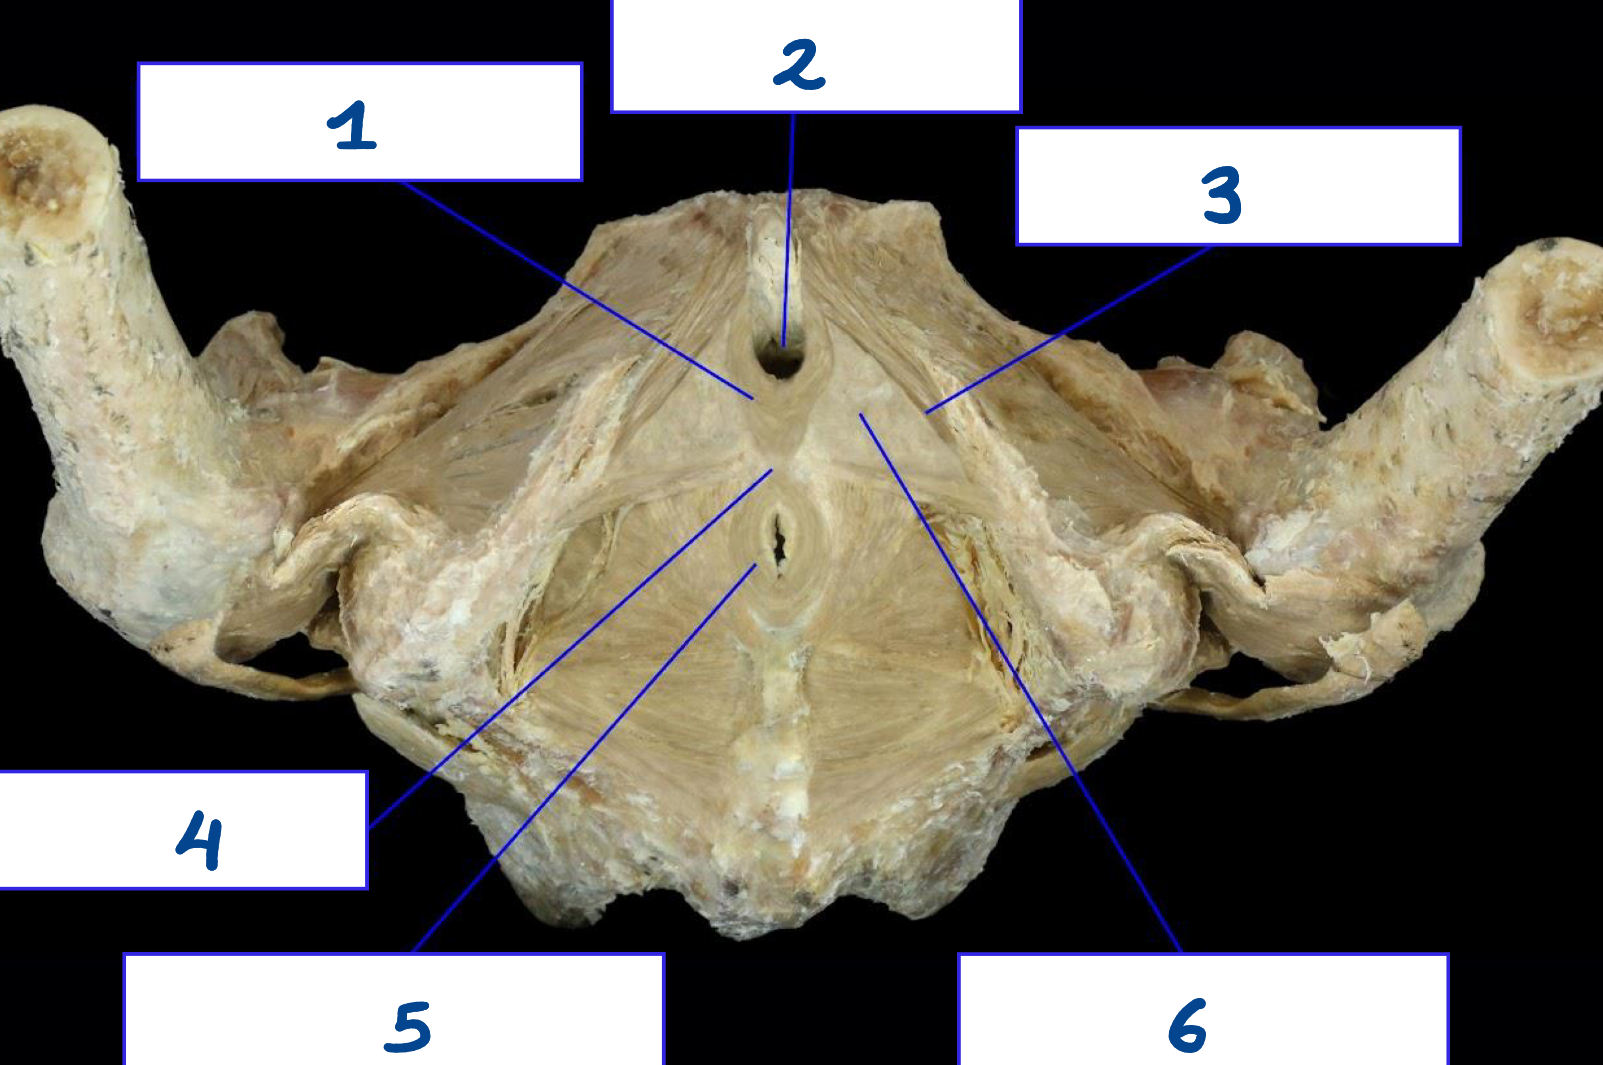

<p>What is structure 1?</p>

What is structure 1?

Acetabulum

<p>What is structure 2?</p>

What is structure 2?

AIIS

<p>What is structure 3?</p>

What is structure 3?

ASIS

<p>What is structure 4?</p>

What is structure 4?

Arcuate line

<p>What is structure 5?</p>

What is structure 5?

Coccyx

<p>What is structure 6?</p>

What is structure 6?

Iliac crest

<p>What is structure 7?</p>

What is structure 7?

Iliac fossa

<p>What is structure 8?</p>

What is structure 8?

Ischial spine

<p>What is structure 9?</p>

What is structure 9?

Obturator foramen

<p>What is structure 10?</p>

What is structure 10?

Pectineal line

<p>What is structure 11?</p>

What is structure 11?

Pubic symphysis

<p>What is structure 12?</p>

What is structure 12?

Pubic tubercle

<p>What is structure 13?</p>

What is structure 13?

Sacral promontory

<p>What is structure 14?</p>

What is structure 14?

Sacro-iliac joint

<p>What is structure 15?</p>

What is structure 15?

Sacrum